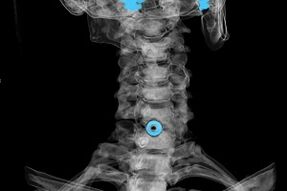

Le diagnostic repose sur les symptômes caractéristiques et sur :

- Rayons X. La méthode est inefficace, surtout dans les dernières étapes du développement de l'ostéochondrose.

- IRM (imagerie par résonance magnétique) de la colonne cervicale. Une méthode qui permet de visualiser les structures osseuses, les hernies discales, leur taille et leur sens d'évolution.

- Tomodensitométrie. Une solution moins efficace que l’IRM car la présence et la taille des hernies sont difficiles à déterminer.